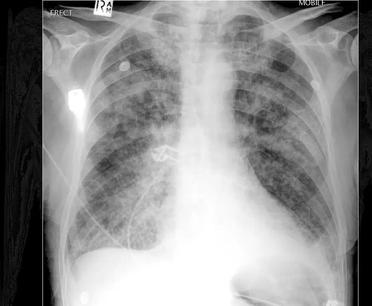

Broken heart syndrome, a known as takotsubo cardiomyopathy or stresscardiomyopathy, is a temp heart condition characteri symptoms resembling a heart attack, such as che shortness of breath, and ra irregular heartbeat, discov Japan in 1991 It occurs in response to intense emotional or physical stressors, which can trigger a surge of stress hormones like adrenaline, temporarily damaging parts of the heart Numerous factors, including

sudden illness, major surgery, or the loss of a loved one, can precipitate this syndrome. Women, particularly those over 50 and individuals with preexisting mental health conditions, are more susceptible Complications may include pulmonary Edema, low blood pressure, arrhythmias, and in rare cases, heart failure or blood clots in the heart.

Recovery typically takes about 4 to 6 weeks. Despite its potentially alarming presentation, broken heart syndrome is usually reversible, and most individuals recover fully with appropriate medical management and support

Diagnosis typically involves blood tests, electrocardiograms (ECG), coronary angiograms, and echocardiograms. Treatment mirrors that for a heart attack until a clear diagnosis is established with